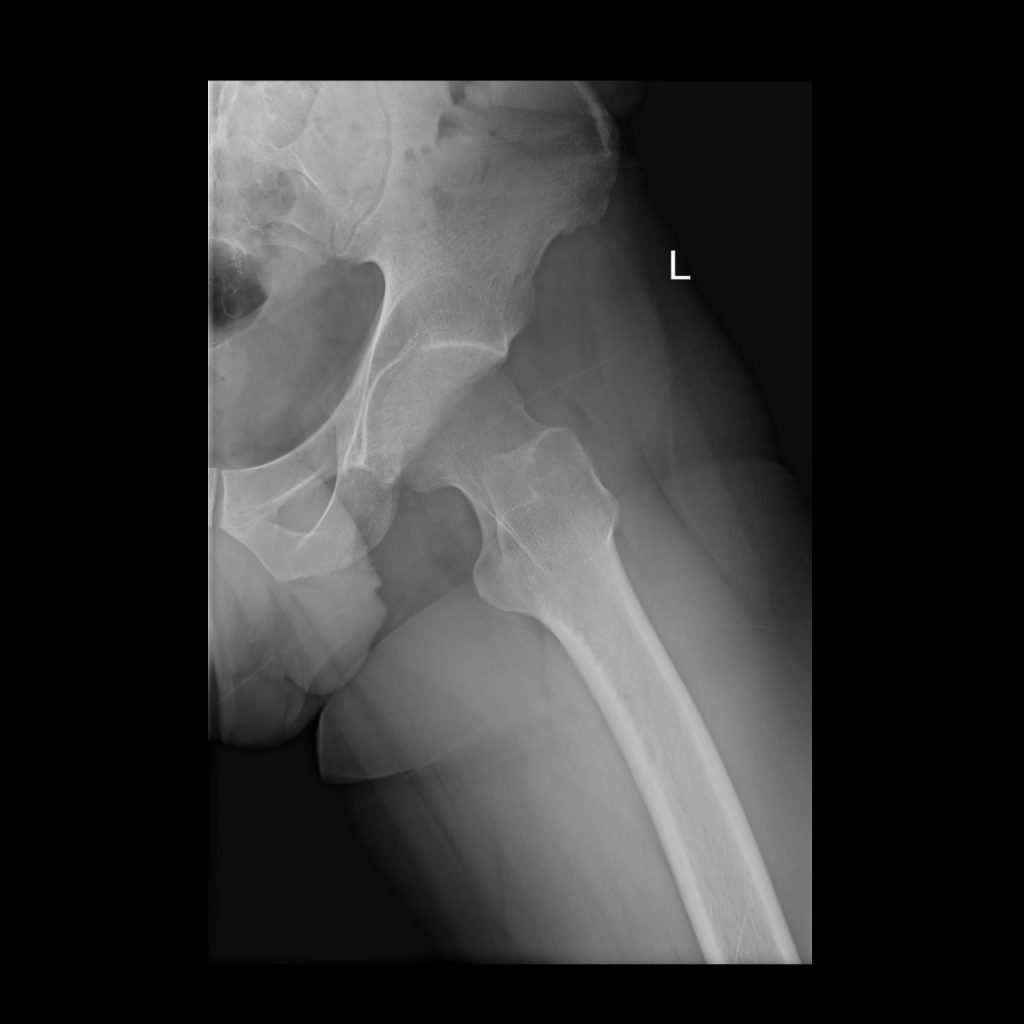

TRANSIENT OSTEOPOROSIS OF THE HIP

This is a curious condition without obvious etiology. It is characterized by loss of bone density in one of the hips of the affected person. It is usually found in middle aged men and sometimes in pregnant women. The condition usually clears up within a few months. It can be painful if the bone is under strain therefor, treatment consists of partial weight bearing to alleviate pain.